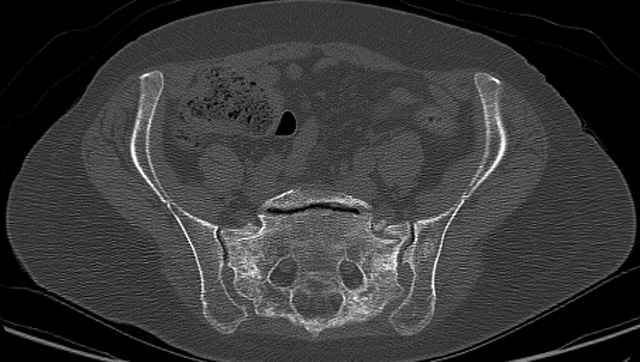

54 yo Female Fell c/o Pain

Initial Films

?Instability on Exam - Limited by Pain

NonOp Initial Mgmt

3 Months After Fall

Continued Pain & Immobility

(+) Instability to Compressive Manual Exam

Pelvic CT Scan - 3 Months After Fall

Sacral Injuries

Ramus Fractures